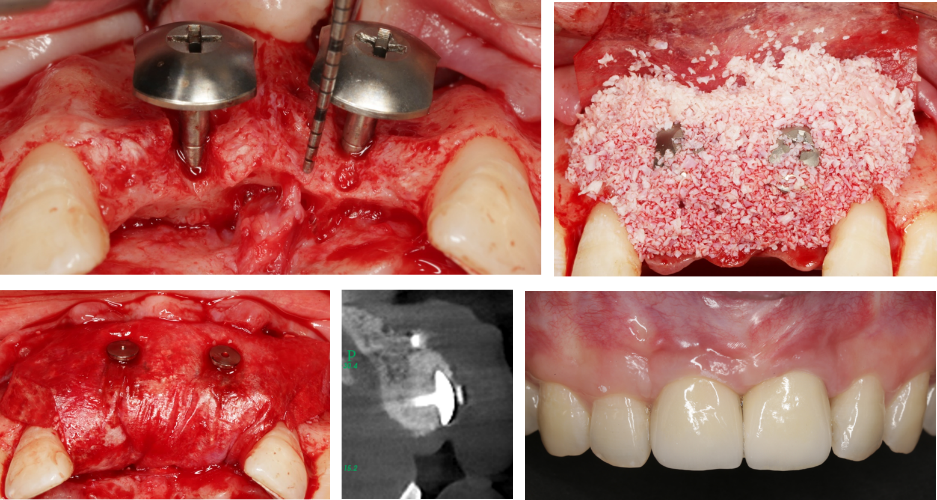

His long-term work focuses on severe jaw defect reconstruction and geriatric dental implantology. Guided by a stability-centered treatment philosophy, he helped establish a pure artificial bone substitute pathway for severe alveolar bone defects, reducing the need for autogenous bone harvesting.

Stability-centered reconstruction strategy for major alveolar and jaw defects with dedicated surgical materials.

03 Pure Artificial Bone ReconstructionArtificial bone powder reconstruction route for severe alveolar defects, reducing the need for donor-site harvesting.

Book material based on the new tent screw technique for severe alveolar bone defect repair.

Anatomical Zoning & Bone AugmentationClinical decision material for bone augmentation based on anatomical zones and operative planning.